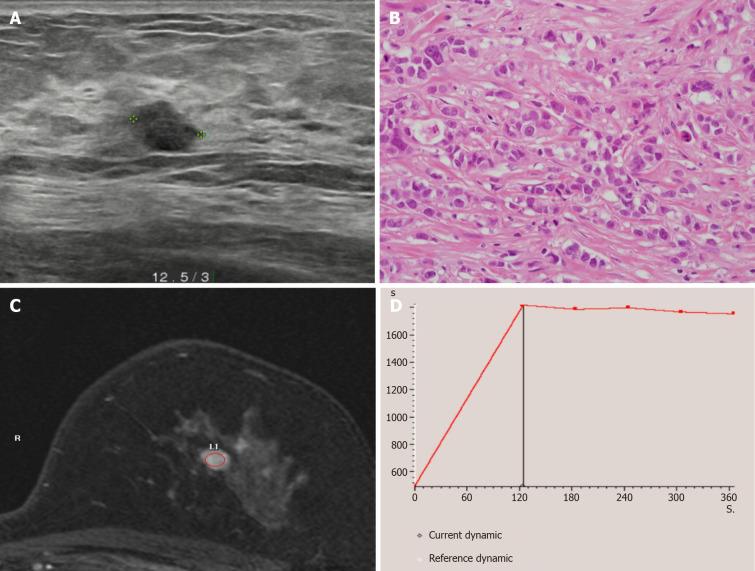

Due to the increasing number of diagnosed nonpalpable breast cancer cases, wire localization has been commonly performed for surgical guidance to remove nonpalpable breast lesions. This report presents a rare case of localized wire migration to a subcutaneous lesion of the upper back in a breast cancer patient undergoing breast-conserving surgery.

A 48-year-old female was scheduled for breast-conserving surgery for left breast cancer. Ultrasonography guided wire localization was performed intraoperatively by surgeon to localize the nonpalpable breast cancer. After axilla sentinel lymph node biopsy, we realized that the wire was not visualized. The wire was not found in the operation field, including the breast and axilla. Breast-conserving surgery was performed after wire re-localization. Intraoperative chest posteroanterior view revealed that the wire was located on the level of midaxillary line. Two days after the operation, a serial simple X-ray revealed that the wire was located on the subcutaneous lesion of the back. The wire tip was palpable under the skin of the upper back, and the wire was removed under local anesthesia.